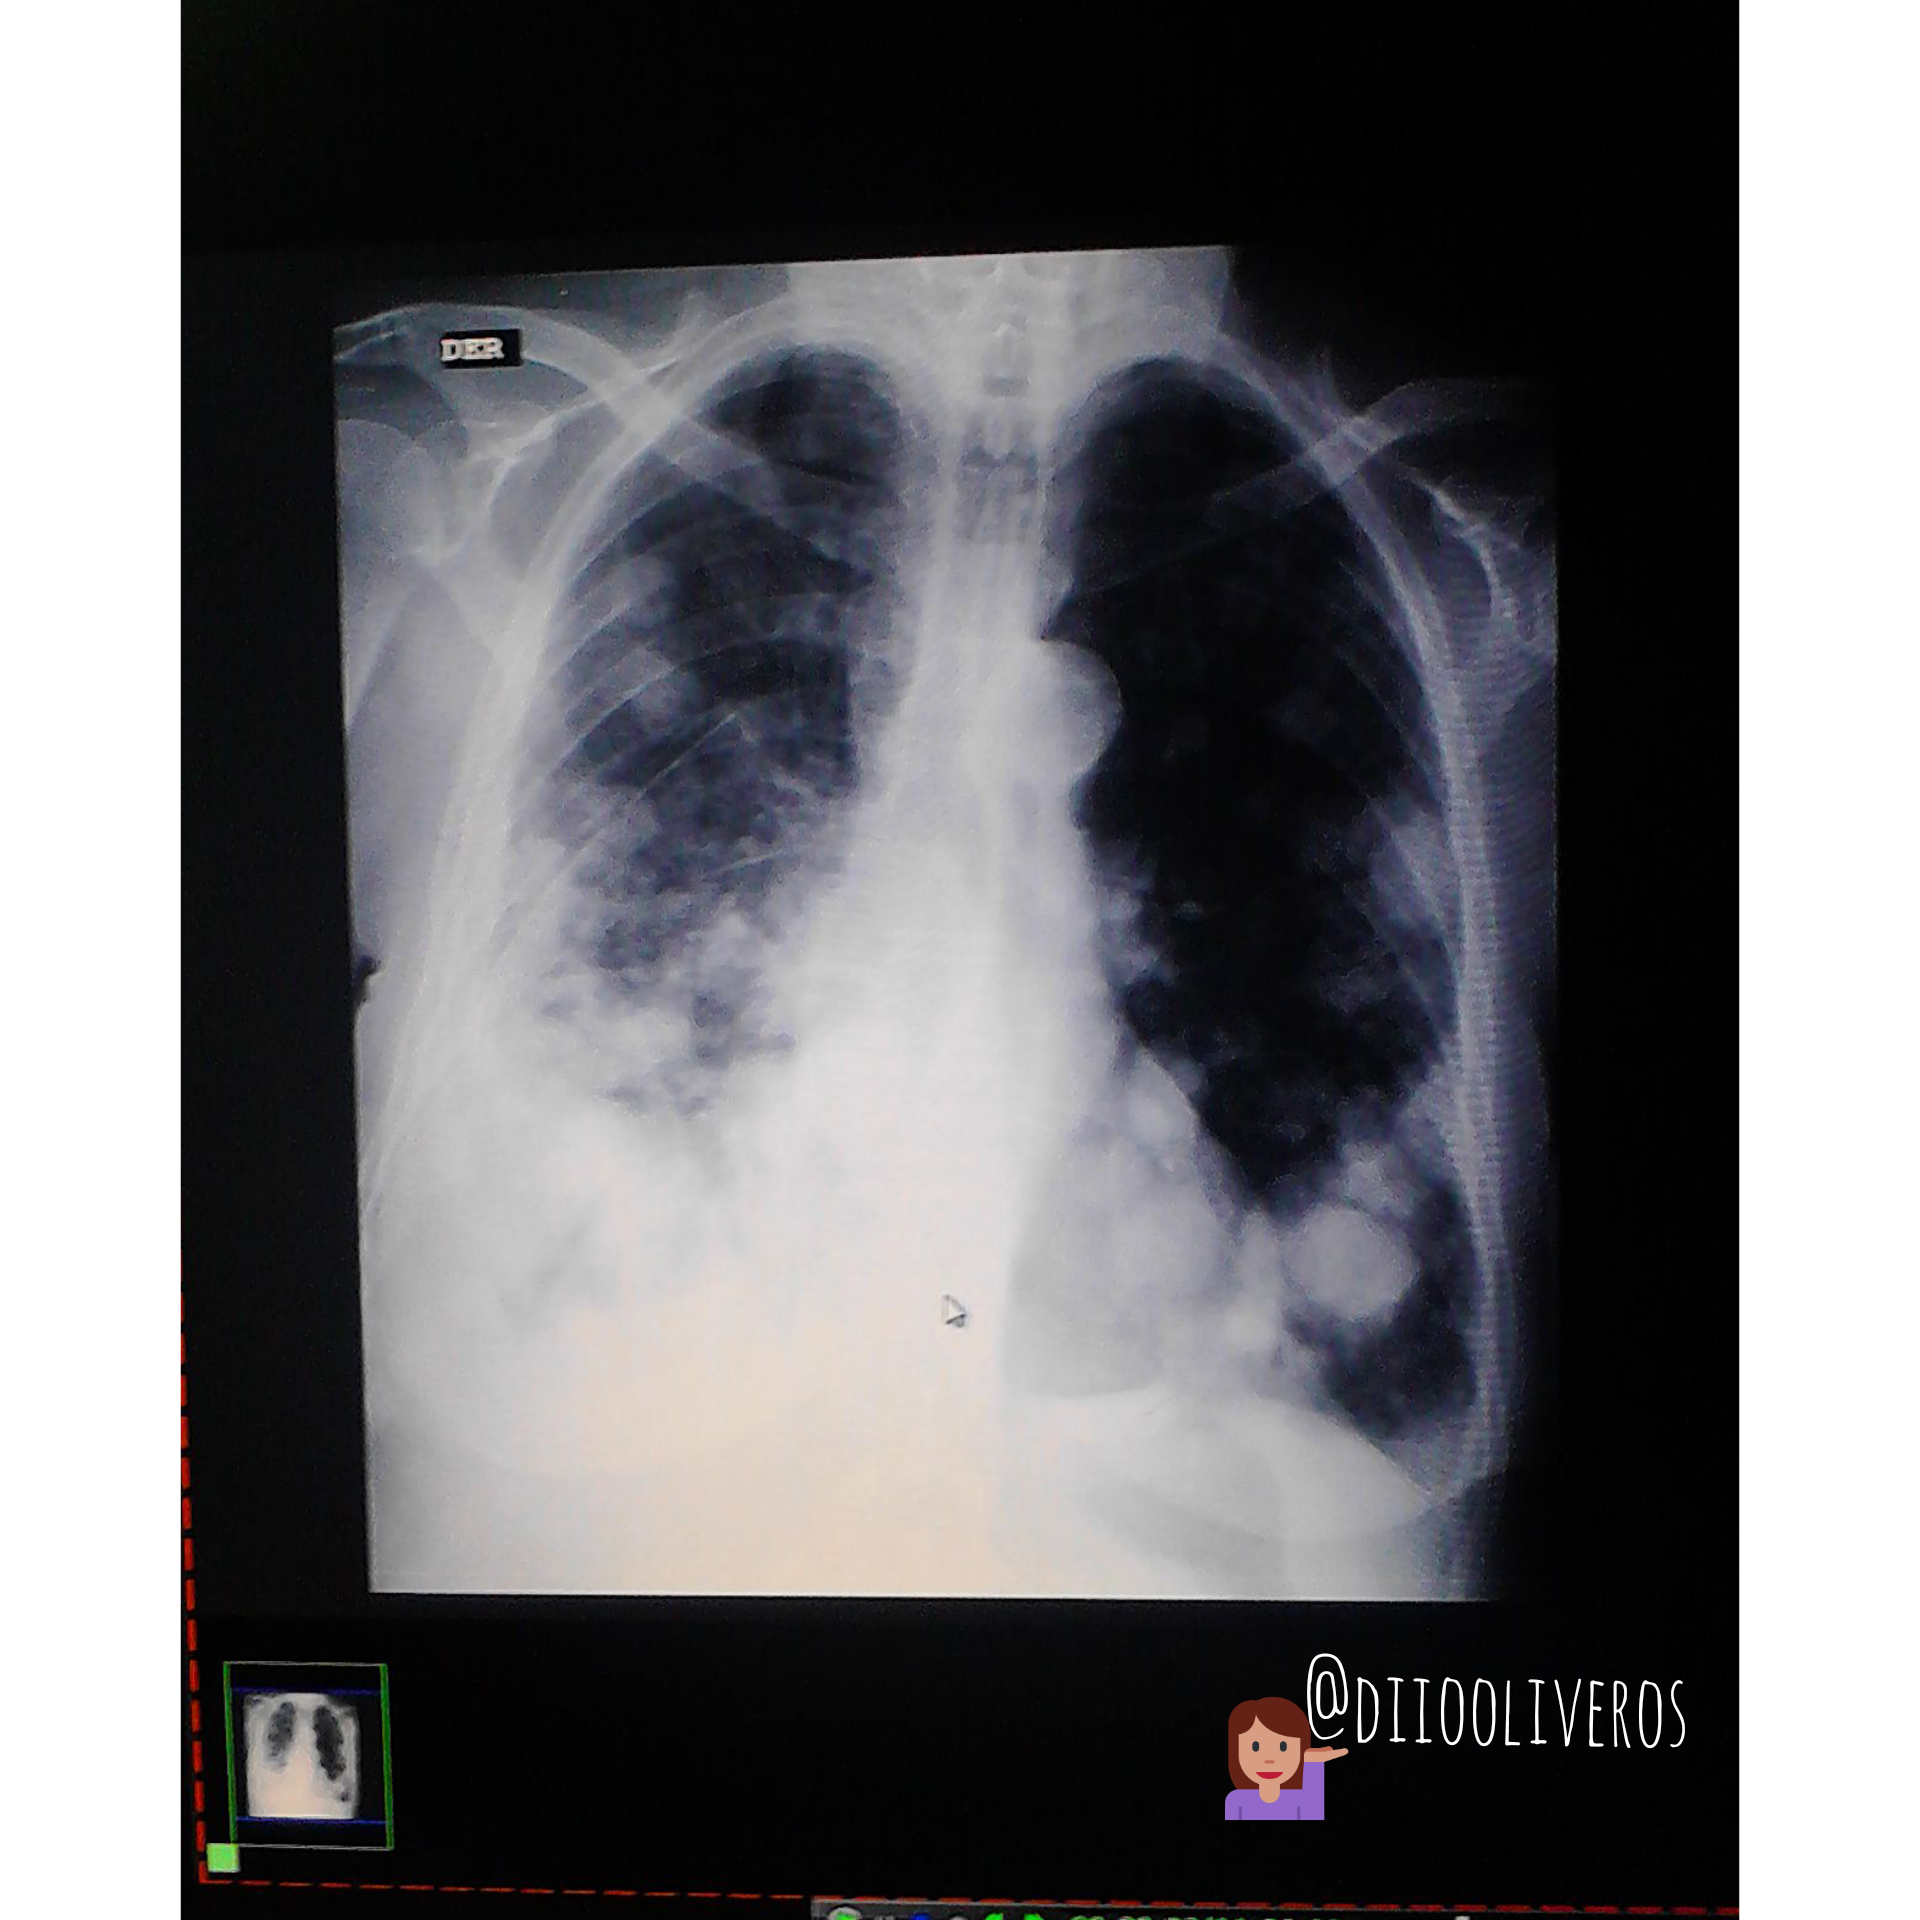

Cáncer de pulmon visto desde Rayos X

Saludos a todos. Esta vez quiero mostrarles como se observa un cáncer de pulmón visto desde un estudio radiografico (Rayos x) En la siguiente imagen tomada con mi telefono…